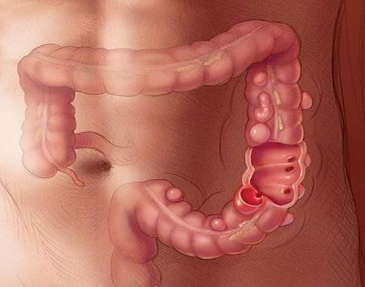

Colon

Los pacientes pueden presentar múltiples patologías en el Colon que requieren de manejo quirúrgico:

Enfermedad Diverticular y Diverticulitis

Los divertículos son dilataciones de la mucosa colónica, los cuales pueden ser múltiples y presentar como complicación sangrado o inflamación y perforación. Esta enfermedad puede operarse de forma programada, cuando estos divertículos no presentan complicación en agudo; sin embargo, en algún momento ya han generado cuadros previos de inflamación y se realiza una resección del segmento afecto con inmediata conexión de los segmentos sanos. También pueden requerir de manejo quírurgico de urgencia en el caso de presentar inflamación severa o perforación, en donde en base a los hallazgos se ofrece la mejor opción quirúrgica a los pacientes.

Cáncer

El cáncer de colon tiene actualmente una alta frecuencia y en estados avanzados tiene un pronóstico desfavorable, es por ello, que se requiere de un diagnóstico y tratamiento oportuno con la finalidad de obtener los mejores resultados quirúrgicos y la mayor sobrevida para el paciente. Es por ello que se ofrece un manejo integral mediante un diagnóstico temprano por Colonoscopía y manejo quirúrgico seguro, adecuado y oportuno para el paciente.

Estomas

Los pacientes pueden ser portadores de estomas por múltiples causas (trauma abdominal, procesos inflamatorios agudos, perforación intestinal o colónica, cáncer). Sin embargo, en la mayoría de los casos se puede retirar el estoma y volver a conectar el intestino o colon, restableciendo el tránsito intestinal normal, para lo cual llevamos una serie de estudios preoperatorios de Imagen y Endoscopía, con la finalidad de ofrecer la mayor seguridad y asegurar los mejores resultados para el paciente.

Este tipo de cirugías se pueden llevar a cabo mediante Laparoscopía o realizarse cirugía abierta, por lo que se tiene que valorar cada caso en particular, con el fin de ofrecer los mejores beneficios, los menores riesgos y la mayor seguridad para el paciente.